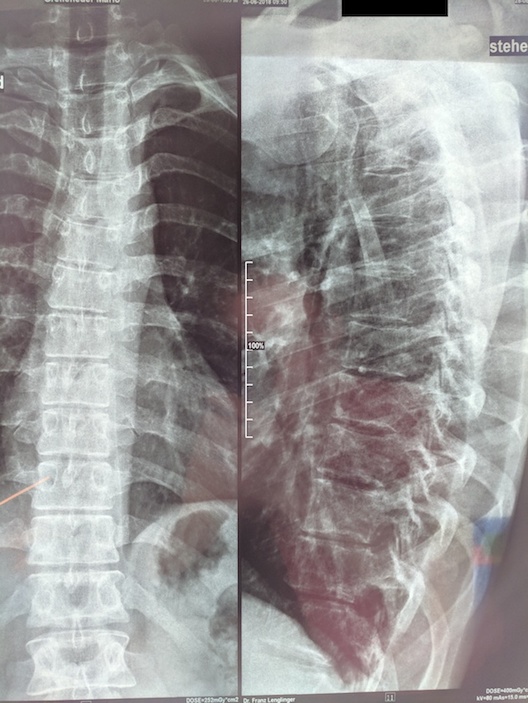

Nachdem ich seit mehreren Wochen bzw. Monaten keine Besserung feststellen konnte, hat mir mein Hausarzt endlich eine Überweisung zu einem Orthopäden (leider kein Skoliose-Spezialist) ausgestellt, außerdem hat er initial ein Röntgen veranlasst, dessen Bilder ich angehängt habe.

Lt. dem radiologischem Bericht handelt es sich hier nur um eine "leichte" linkskonvexe Skoliose, wobei hier auch nur die Brustwirbelsäule abgebildet ist.

Für mich wäre jetzt in erster Instanz interessant, ob hier anhand der Bilder überhaupt Handlungsbedarf in Richtung Skoliose (Schroth etc.) besteht. Ich habe leider kein Ganzkörper-Röntgen, aber vielleicht kann man anhand dem BWS-Röntgen ja die Grad abschätzen? Ich habe mich zwar schon ein wenig in das Thema eingelesen, aber ich fühle mich diesbezgl. noch ein wenig uninformiert - mein Hausarzt ist leider auch keine große Hilfe und er meint, ich solle abwarten und mir keine Sorgen machen. Leider sieht man am Röntgen ja keine Weichteile, aber theoretisch könnte hinter meinen Beschwerden ja auch ein Bandscheibenvorfall o.Ä. liegen, allerdings habe ich keine Ausstrahlungen bzw. neurologische Symptomatik.